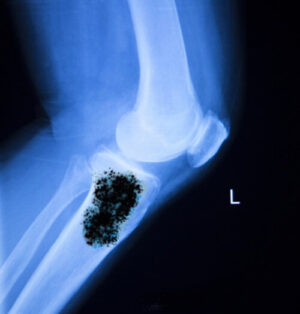

- рентгенографическое исследование скелета (для выявления онкообразований кости и оценки состояния костной ткани);